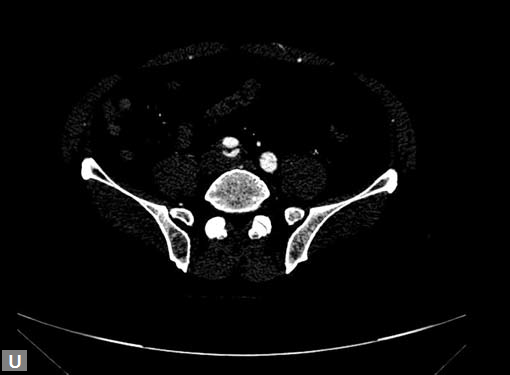

Connective tissue disease, hypertension and iatrogenic (Figs 19K to L) injury are the common causes for dissection. Radiologist not only establishes the diagnosis, also evaluates the extent of dissection, presence of thrombosis particularly in false lumen. In case of type A dissection, involvement of aortic root is determined. Relation of thrombosed lumen and ostia of coronary vessels, cephalad branches (Figs 19N, R to V) of aorta is determined. Most of the occasions membrane is demonstrated. Spiral nature of the membrane can be seen

Double barrel appearance is seen on coronal and sagittal

images. Type B dissections can extend even to common

iliac arteries bilaterally. Superiorly it can extend to involve

common carotid and vertebral arteries.

Figs 19A to Y (A to C) Scannogram (A), plain (B) and contrast study (C) show partial anomalous pulmonary venous connection; (D to F) Heterotaxy; (G) Aortic occlusion; (H and I) Aortic stents; (J) Aortic dissection with ‘Benz’ sign due to second dissection within the true lumen; (K, L and M) Aortic dissection with thrombus in pseudolumen following catheter angiogram; (N) Aortic dissection involving common carotid arteries and subclavian artery; (O, P, Q and R) Aortic dissection with right renal artery arising from true lumen and left renal artery from false lumen; (S, T, U and V) Stanford B dissection with extension Y to iliac vessels; (W to Y) Aneurysmal dilation of ascending aorta